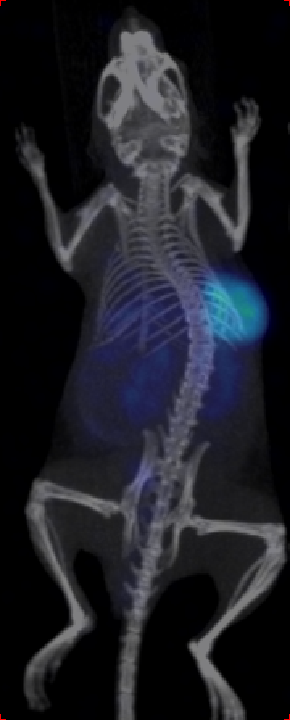

Through quality and process explorations with Zr-89-marked antibody conjugates, highly emissive-pure radiodiagnostic drug molecules are obtained and supplied for preclinical animal imaging and biodistribution studies, as well as subsequent IIT imaging in the clinic.

Rapid validation of Zr-89-marked antibodies

Fast lesion cumulation, most efficient distribution and high targeting ability for xenotransplanted tumor models.